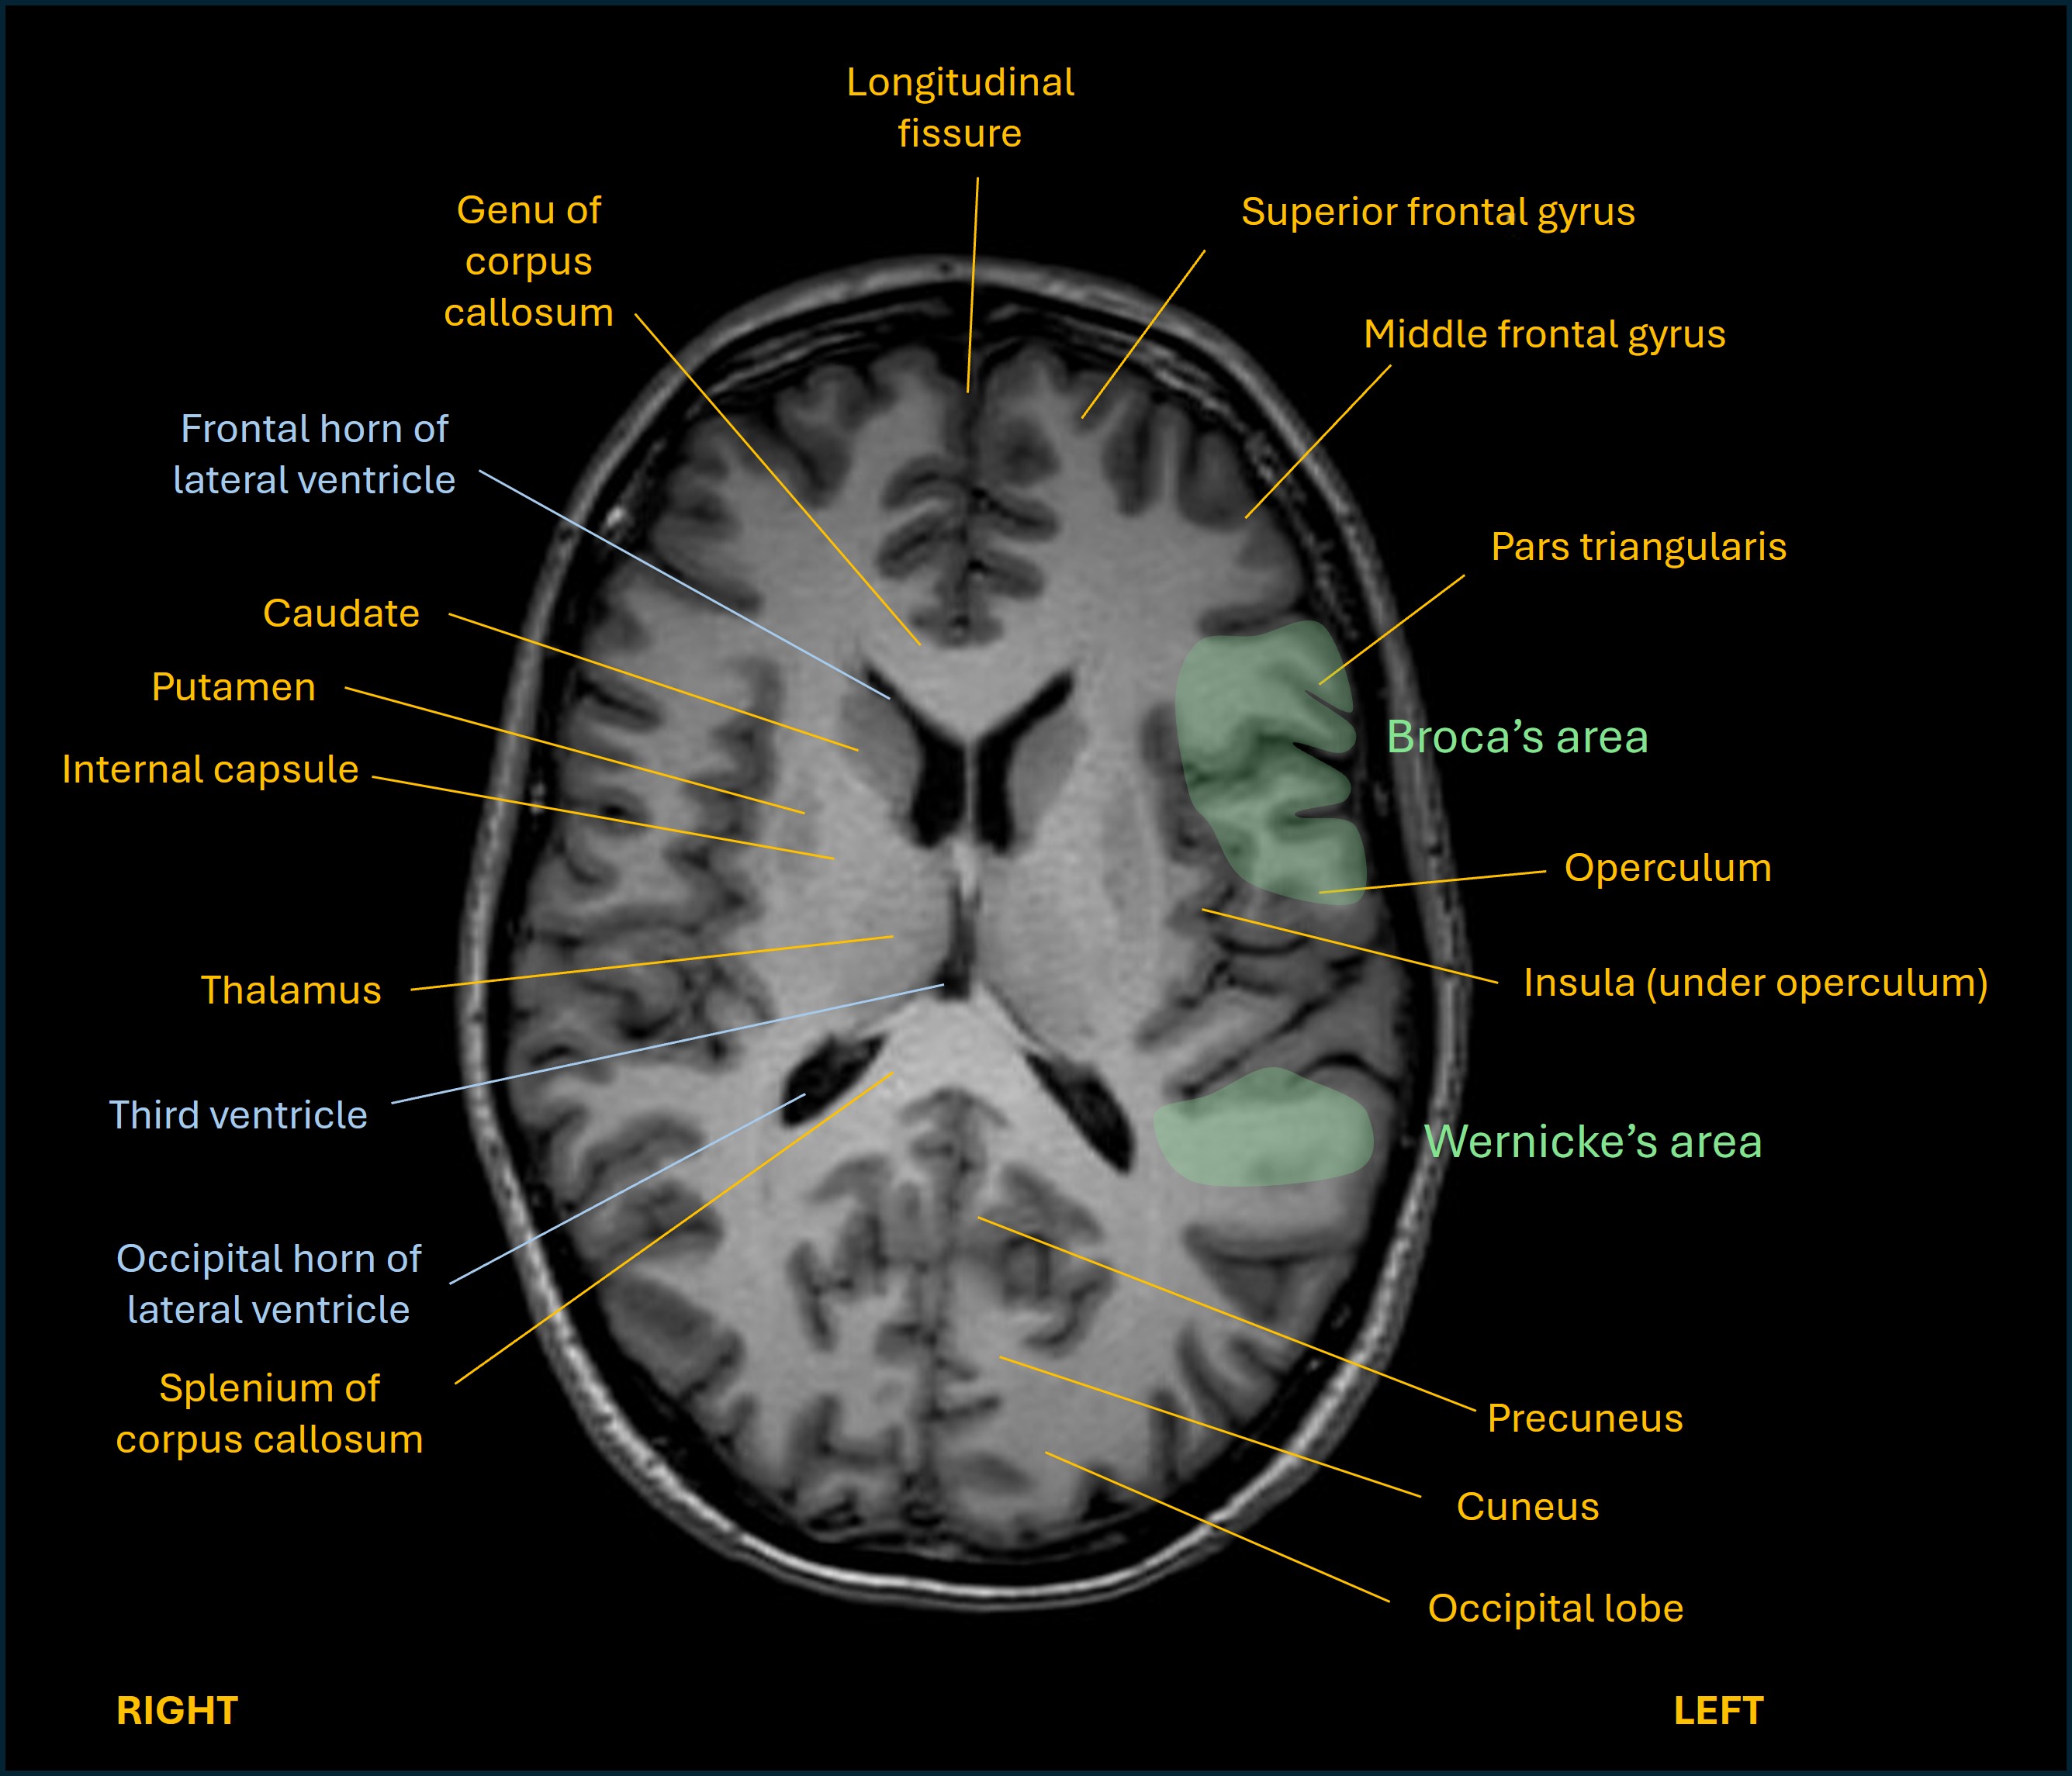

The expressive part relies on a frontal lobe area in the inferior frontal gyrus, known as Broca's area. On lateral views of the brain it looks like an M-shaped gyrus above the anterior part of the Sylvian fissure.

The receptive part is centred in the posterior part of the superior temporal gyrus, known as Wernicke's area. It's at the rear end of the Sylvian fissure, where the temporal lobe and parietal lobe meet.

Axial and sagittal views are shown below on T1 MRI, as well as a close up of the M-shaped region and its three components.

Axial language

Sagittal language